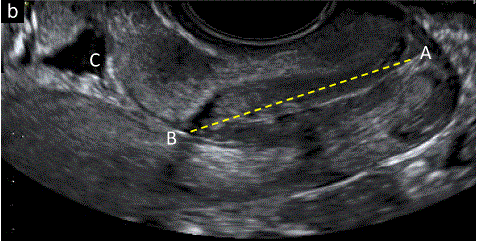

双顶径和头围的测量

双顶径(BPD)和头围是指 胎儿头部的最大对称轴位测量(图1-b)

已经描述了两种测量BPD的技术,将卡尺从外到内(前缘)或从外到外,垂直于中线镰。应根据用于建立诺模图的方法进行测量。

根据CRL和/或腹围(AC)或腹横径调整BPD测量值(TAD)可能有助于早期筛查脊髓脊膜膨出和前脑无裂畸形。

胎儿mt是什么检查什么疼吗【文献学习/规范指南】ISUOG实践指南(2023更新): 11-14周胎儿超声检查(全文)_https://www.jmylbn.com_新闻资讯_第3张

图1 11+0至14+0周胎儿超声检查可获得的测量值。(b) 丘脑水平的胎儿头部横断切面,显示双顶径(BPD)的测量值,卡尺从外到外放置,和头围。在这个平面上可以看到中线大脑镰和丘脑。在一些国家指南中,BPD测量是通过测量外径到内径来实现的。